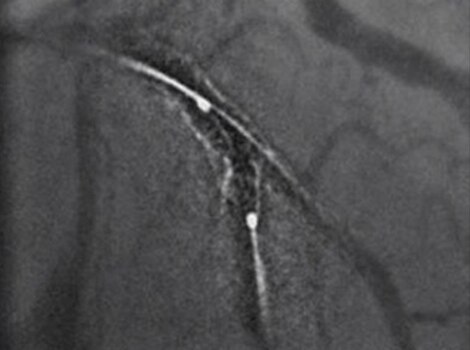

PCI ASSIST13

Help plan, assess and guide interventional procedures with improved visibility up to 85 percent in moving anatomy.

Successful PCI of the stenotic lesions involves planning, guidance, and assessment of the culprit lesion and assessment of the remainder of the coronary tree.

PCI ASSIST6